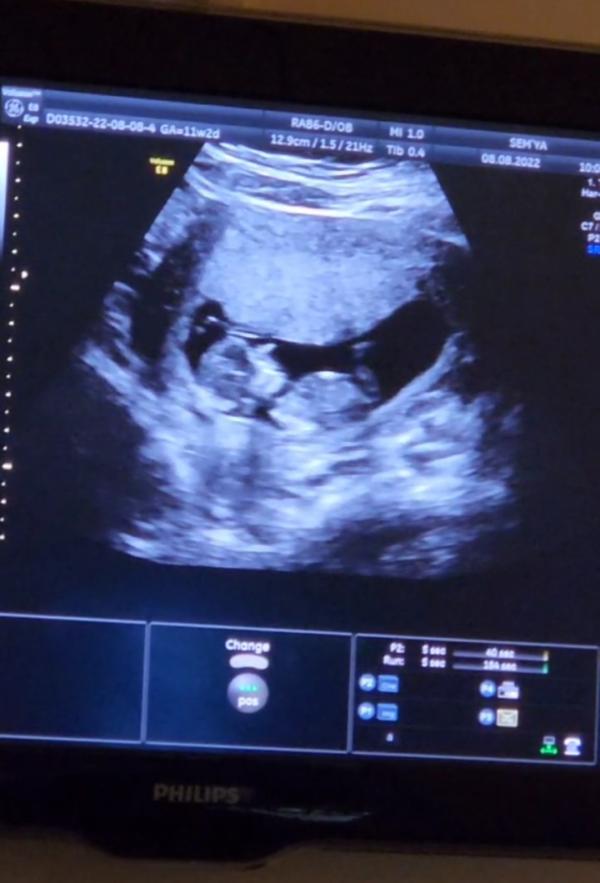

Сегодня ходили с мужем на скрининг первого триместра.

С малышом всё хорошо. Очень активный.

По росту говорят 12 недель есть, а по месячным 11,2

Предположительно мальчик) писюн разглядели даже( на втором фото вид снизу между ножек)....но мне пока что не верится. Через 8 недель второй скрининг будет. Там уже точно узнаем кого мы ждём😊💕🙏